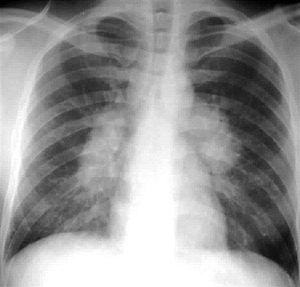

Sarcoidosis is an idiopathic condition characterized by granulomatosus inflammation of multiple organs. Most commonly affected organ is lungs, other organs can also be involved such as liver, spleen, bone, and heart. About 50% of the cases having the disease are asymptomatic, in symptomatic cases the symptoms are cough, fever, arthritis, erythema nodosum, lymphadenopathy, uveitis, interstitial fibrosis, and facial rash. Sarcoidosis may extend to the nervous system involving the optic nerve most commonly followed by trigeminal nerve and lastly the facial nerve, symptoms of neourosarcoidosis are non localizable such as headache, tirdness, weakness, and nausea. This X-Ray is diagnostic for sarcoidosis as it shows the involved lungs with Bilateral hilar lymphadenopathy. Treatment could be by observation as remission could occur over a period of two years, or pharmacologic by using corticosteroids or TNF Inhibitors.